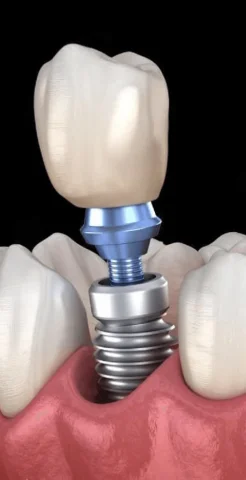

Стоматологічні послуги

У нас працюють 8 дипломованих фахівців, кожен з яких досконало володіє своєю справою: від терапії та гігієни до складної імплантації та ортопедії.

Використовуємо інноваційний цифровий інструментарій, що діє точково: ми зберігаємо здорові тканини зуба, уникаємо перегріву та забезпечуємо максимально швидку реабілітацію.